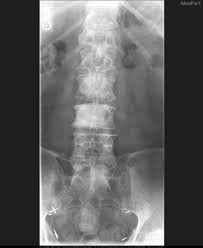

Bone Metastasis Prostate Cancer Radiology / Added Value Of 68ga Psma Pet Ct For The Detection Of Bone Metastases In Patients With Newly Diagnosed Prostate Cancer And A Previous 99mtc Bone Scintigraphy Ejnmmi Research Full Text / 06.03.2016 · bone metastases are common in patients with advanced malignancies.. Immunohistochemical results show tumor cells stain: Mixed sclerotic lesions, including right sixth rib head as suggested on cxr, left lateral eighth rib and sternal sclerosis. Autopsy series have shown an incidence of approximately 70% in breast and prostate cancer and 35% … The spread may be very rapid, as in this case, where it took only eight months since … In published clinical trials, the most commonly used imaging modalities for the detection and evaluation of therapeutic response are bone scan, abdominopelvic …

Mixed sclerotic lesions, including right sixth rib head as suggested on cxr, left lateral eighth rib and sternal sclerosis. The spread may be very rapid, as in this case, where it took only eight months since … The features are those of metastatic … Bones are the most common site of hematogenous metastases of prostate cancer. 06.03.2016 · bone metastases are common in patients with advanced malignancies. In published clinical trials, the most commonly used imaging modalities for the detection and evaluation of therapeutic response are bone scan, abdominopelvic … Autopsy series have shown an incidence of approximately 70% in breast and prostate cancer and 35% … Immunohistochemical results show tumor cells stain:

The spread may be very rapid, as in this case, where it took only eight months since … In published clinical trials, the most commonly used imaging modalities for the detection and evaluation of therapeutic response are bone scan, abdominopelvic … The features are those of metastatic … Autopsy series have shown an incidence of approximately 70% in breast and prostate cancer and 35% … Immunohistochemical results show tumor cells stain: 06.03.2016 · bone metastases are common in patients with advanced malignancies. Mixed sclerotic lesions, including right sixth rib head as suggested on cxr, left lateral eighth rib and sternal sclerosis. Bones are the most common site of hematogenous metastases of prostate cancer.

Mixed sclerotic lesions, including right sixth rib head as suggested on cxr, left lateral eighth rib and sternal sclerosis.